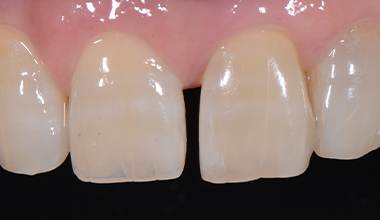

CASE 02

-

치료 전 -

치료 후